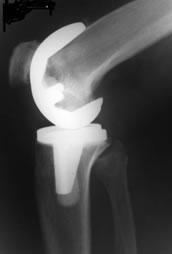

Total knee replacement (TKR), also referred to as total knee arthroplasty (TKA), is a surgical procedure where worn, diseased, or damaged surfaces of a knee joint are removed and resurfaced with artificial smooth and strong materials which are durable and also produce as little friction as possible. The "artificial joint or prosthesis" generally has two components, one made of metal which is usually cobalt -chrome or titanium. The other component is a plastic material called polyethylene

The lower end of the thigh bone (femur) is resurfaced with a metal cap.

The upper end of the leg bone (tibia) is replaced with a plastic and metal implant with cement and or screws.

The back of the kneecap (patella) is also resurfaced with an all-plastic implant. Highly specialized instruments are used that allow precision cutting of the bone so that the new joint fits perfectly. The type of implant used depends on surgeon's preference and patient requirements.)